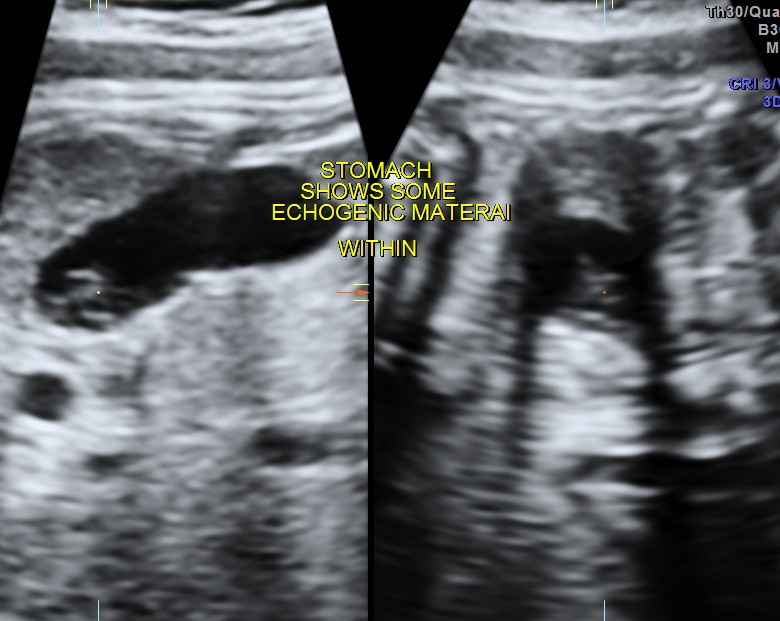

Echogenic material is seen within the stomach.

The following are 3 d images , which prove that this was not an artefact.